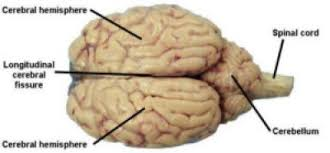

Cerebral hemispheres

cerebrum

conscious brain - the larger of the two, in the front

cerebellum

smaller, back part, lots of folds, coordinates muscle movements and muscel memory

gyri

the ridges - bumps

sulci

the grooves - lines

longitudinal fissure

line in the middle, separates 2 cerebrum

transverse cerebral fissure

separates cerebrum and cerebellum